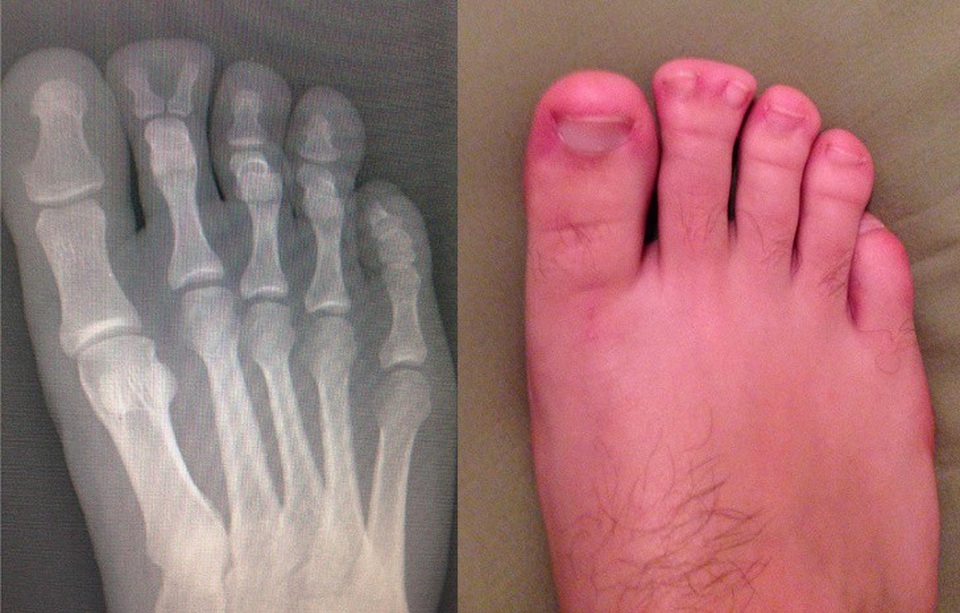

(Dân trí) - Hình ảnh chụp X-quang của những chủ thể đặc biệt như: một chú mèo đang mang thai, bộ phận cơ thể bị dị tật bẩm sinh hay thậm chí là bụng của cô bé nuốt nhầm chiếc bấm móng, được tổng hợp dưới đây, sẽ giúp bạn như bước vào một thế giới mà mình chưa từng biết!